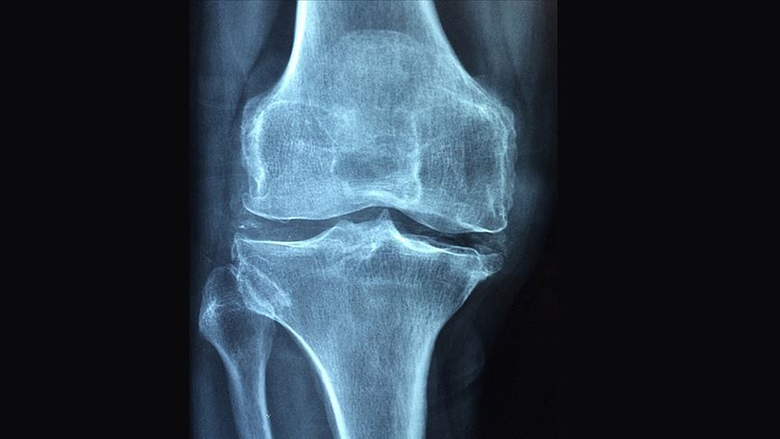

Çalışmaya ilişkin bilgiler veren Prof. Dr. Fırtına, kemik erimesinin dünya genelinde yaklaşık 200 milyon kişiyi olumsuz etkilediğini söyledi. Osteoporozun tedavisi için şu anda yan etkisi olmayan etkili bir ilacın bulunmadığını belirten Prof. Dr. Fırtına, "Osteoporoz, çoğu zaman sadece kemik yoğunluğundaki azalma olarak algılanıyor; oysa hastaların günlük yaşamında çok daha derin etkiler oluşturan bir tabloyla karşı karşıyayız. Bu hastalık, kişinin en basit hareketlerini bile çekinerek yapmasına neden olabiliyor. Yürümek, eğilmek, eşya taşımak ya da tek başına dışarıya çıkmak gibi sıradan görülen davranışlar, zamanla ciddi bir kaygı kaynağına dönüşebiliyor. Kırık riskiyle yaşamak, hastalarda yalnızca fiziksel değil, duygusal ve sosyal açıdan da önemli bir yük oluşturuyor" diye konuştu.